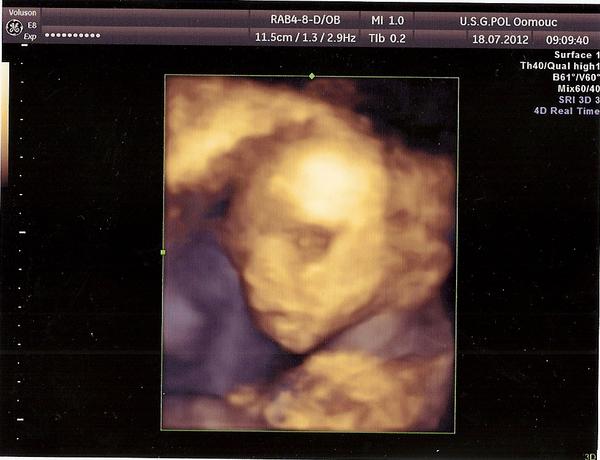

Ahoj holky tak jsem byla dnes na poslední genetice a naše malá je v pořádku a přikládám fotečku 🙂 😉